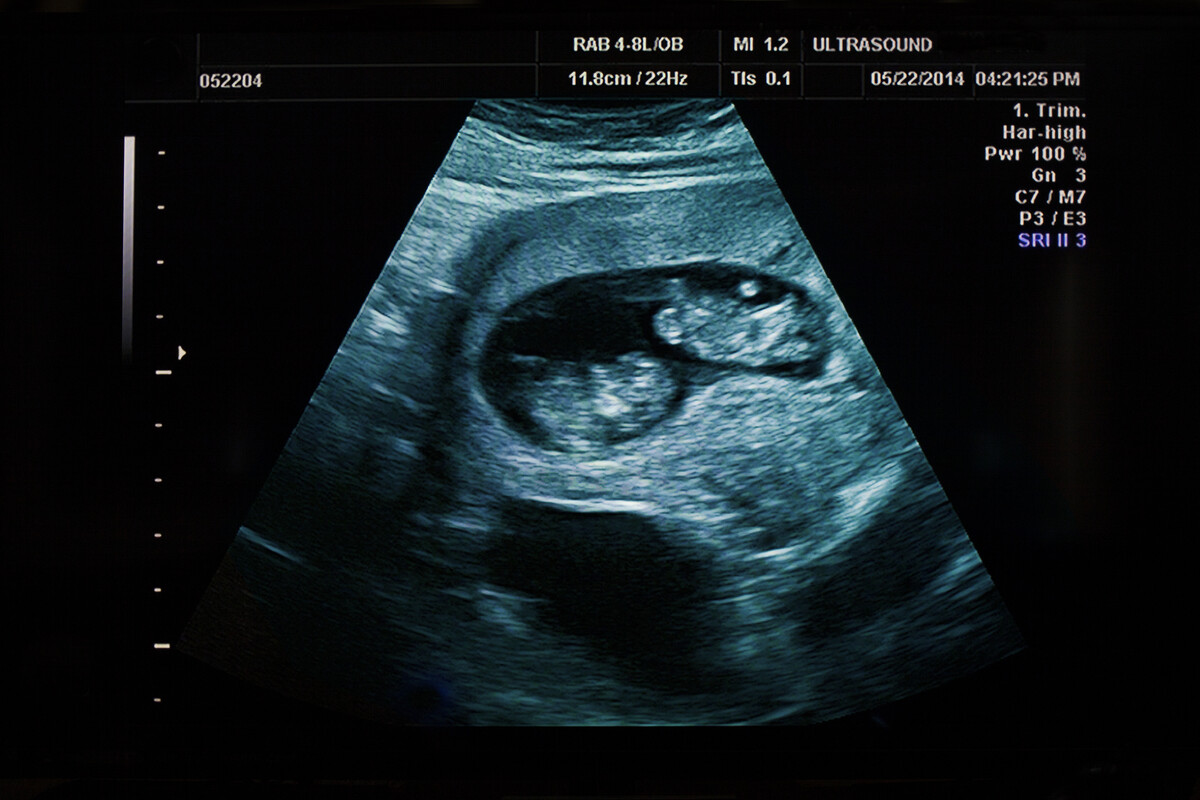

Apesar da condição incomum, Ana Paula leva uma vida completamente saudável. Seus órgãos reprodutivos, como ovário e útero, funcionam normalmente, e ela conseguiu engravidar durante as pesquisas, dando à luz um bebê saudável. Contudo, é a primeira mulher quimérica espontânea com gestação bem-sucedida documentada no mundo. É por isso que esse caso é considerado inédito e surpreendente pelos pesquisadores.

Além disso, também foi realizada uma análise genética na criança que mostrou um resultado dentro do esperado, com metade dos cromossomos herdados da mãe e a outra metade do pai. Para os médicos envolvidos no estudo, essa descoberta pode ajudar a ampliar o entendimento sobre imunidade, transplantes e reprodução.